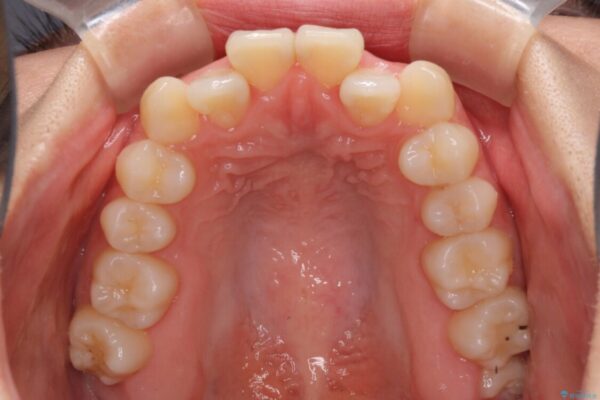

上の真ん中から2番目の歯が、他の歯よりも内側にある状態(舌側転位)だったため、インビザライン治療だけで無理に動かそうとすると歯髄壊死を起こすリスクが高いと判断。上顎前歯をワイヤー矯正で整えてから、全体をインビザライン治療で調整した事例です。

| 治療内容 | ワイヤー矯正を併用し、リスクを回避しながらのインビザライン矯正治療 |

| 概算治療費 | 950,000円(※税不明・費用は治療当時の料金) |

| 治療回数 | 10~30回 |

| 治療期間 | 1年9ヶ月 |